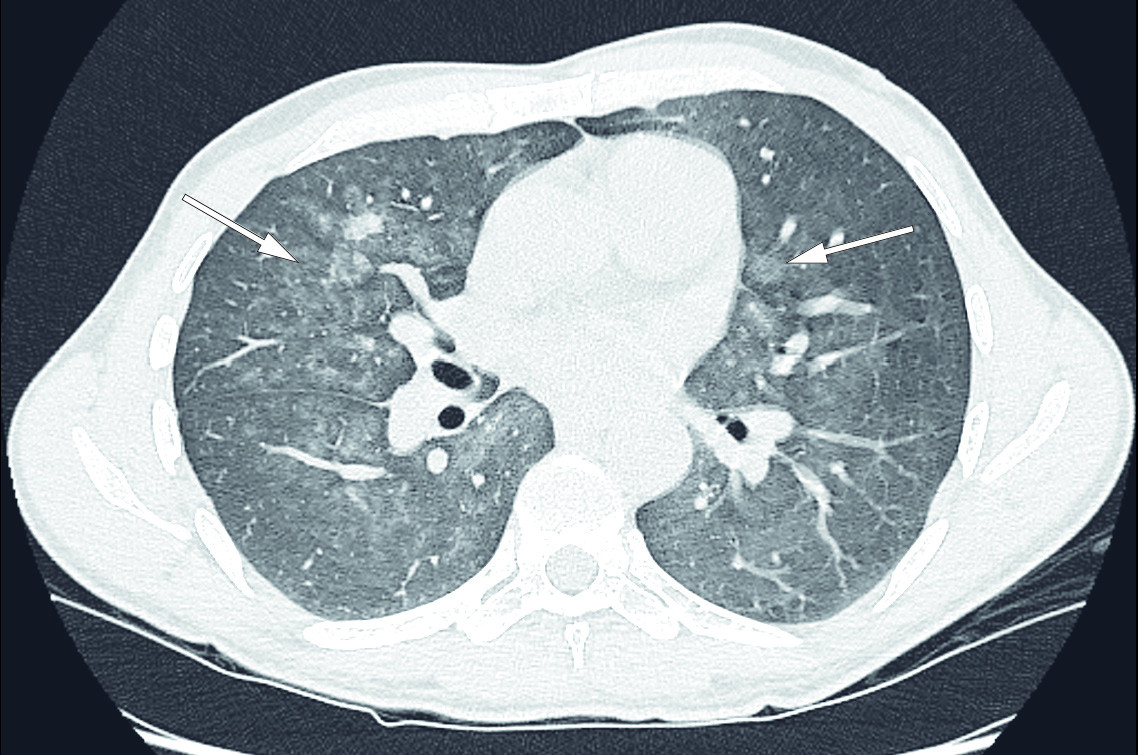

A new CT thorax performed four weeks after the last scan showed that bilateral, patchy ground glass opacities had appeared in the mid fields of the lungs (Figure 2). In addition to the differential diagnoses described on PET-CT, interstitial lung disease and bleeding due to vasculitis were proposed as differential diagnoses.

The patient deteriorated rapidly and was admitted to a local hospital five days later. The following day he was transferred to the department of respiratory medicine at a large hospital for further assessment. Based on the findings available at that point, an interstitial lung disease was suspected. Despite elevated ACE values, the clinical and radiological picture was not consistent with sarcoidosis. Infections, including Pneumocystis jirovecii pneumonia, were also considered sequentially. There was no evidence that the patient's immune defence was reduced.